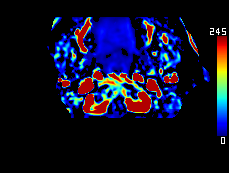

DeepClue-Precise CT 측부혈류영상

Perfusion CT를 이용한 측부혈류영상

동맥기

모세혈관기

조기정맥기

후기정맥기

지연기